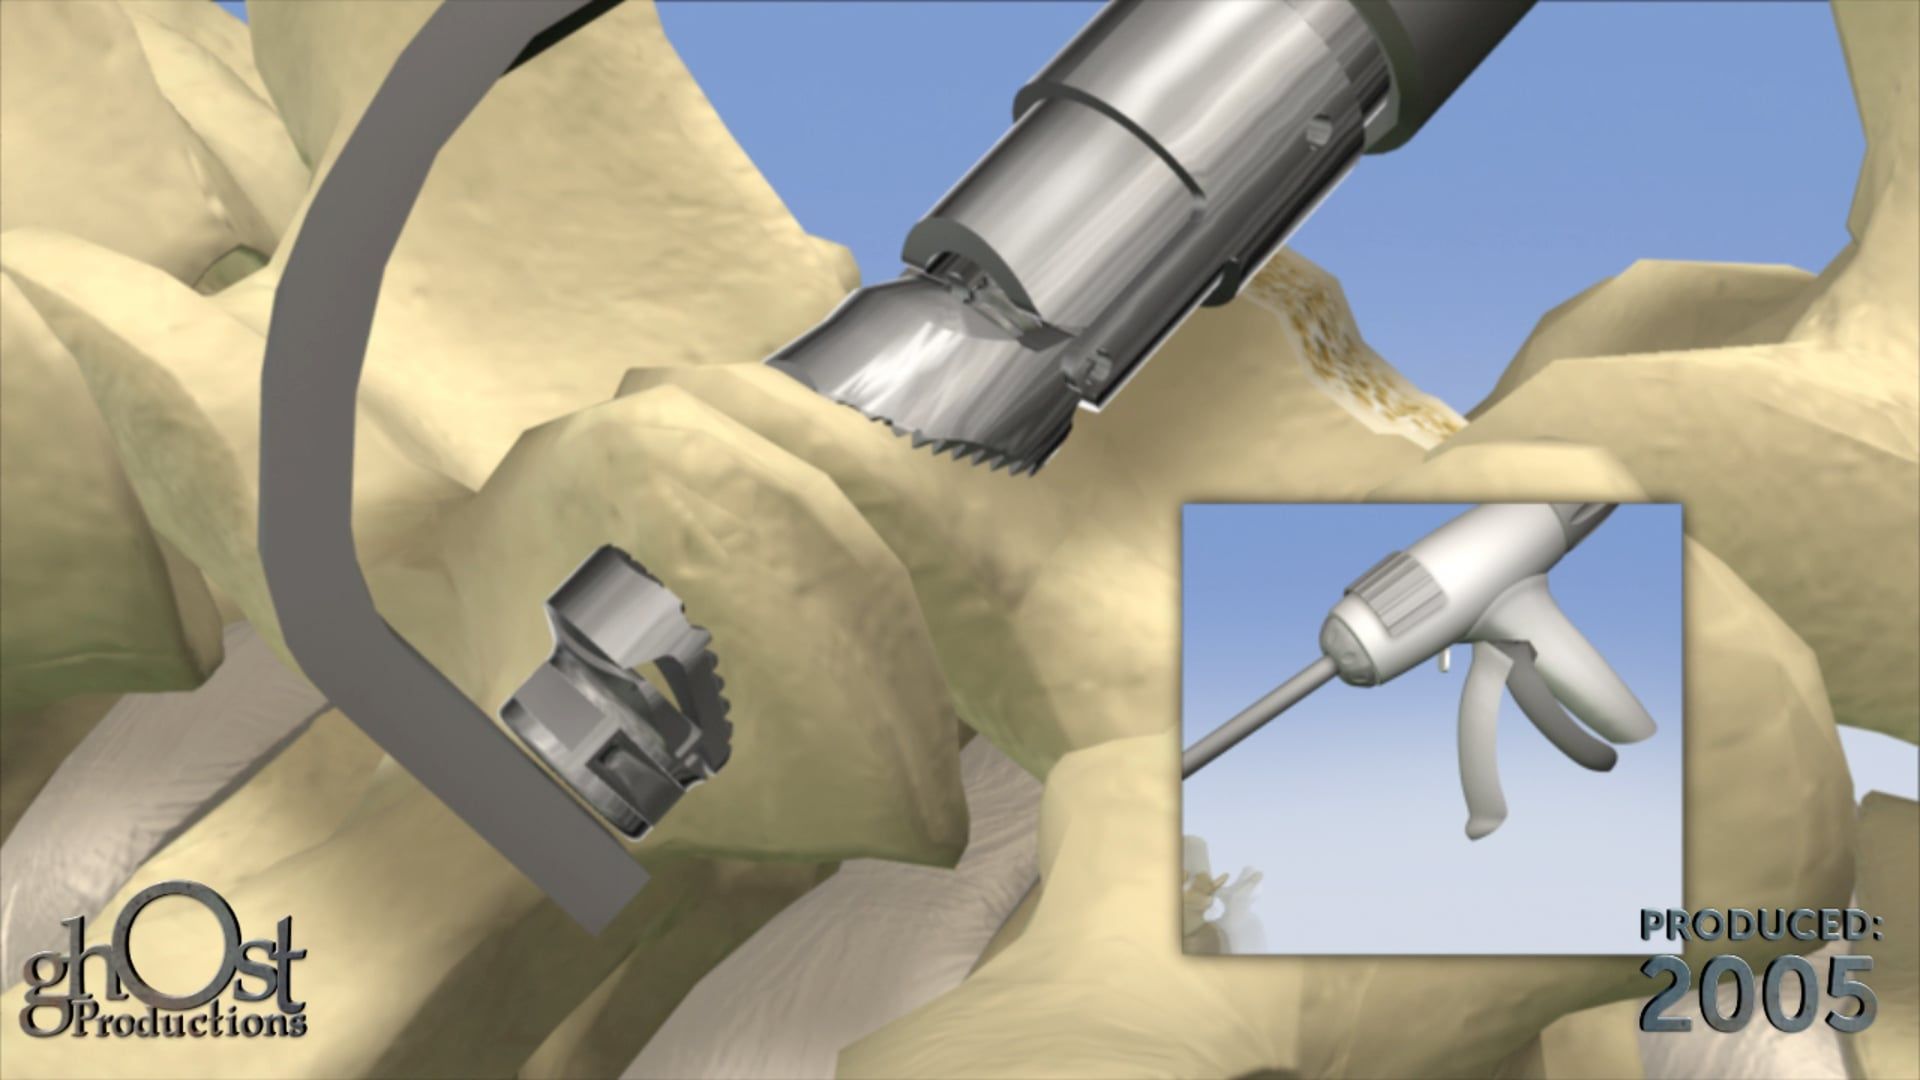

Ghost Productions, a leading medical animation company, created a stunning animation to showcase their talents at the 2009 American Association of Orthopedic Surgeons (AAOS) in Las Vegas. The animation features a character who suffers from multiple bone fractures and undergoes surgical repairs in under 3 minutes. The video highlights various orthopedic surgeries, including clavicle, shoulder, wrist, fibula, tibia, knee, femur, hip, spine, and hand surgeries. The animation is medically accurate and showcases Ghost Productions' expertise in the field of orthopedic surgery. This video is a testament to the company's commitment to creating high-quality medical animations that educate and inform healthcare professionals and patients alike.

Ghost Productions built this medical animation from the ground up to showcase the talents of Ghost Productions at the 2009 American Association of Orthopedic Surgeons (AAOS) in Las Vegas. Instead of showing pre-existing client work in our reel, we thought it would be more fun to make a character animation, break nearly every bone in his body, and then surgically repair him in under 3 minutes.

3:31 - Hip Surgery, Hip Implant

3:56 - Spine Surgery, Disc Replacement